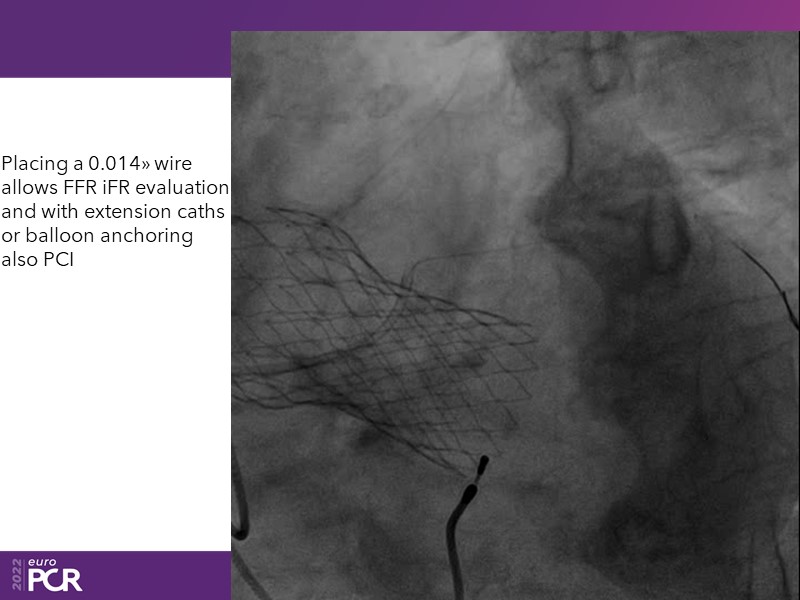

Consult this session to learn how to contribute to streamlined pre- and post-TAVI patient pathways, to discover updates on the optimised TAVI procedure and appreciate the variances in different valve designs and the long-term patient outcomes, as well as to discuss the right time of PCI in TAVI patients (steps on the procedure).

- To discuss the right time of PCI in TAVI patients (steps on the procedure)